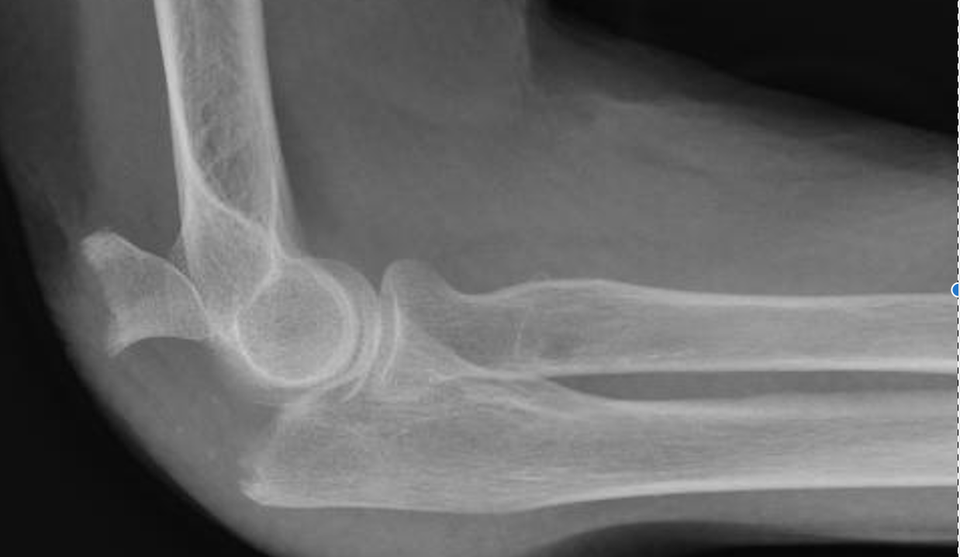

Fractures du COUDE Fractures distales de l humérus Fracture Coude Traitement La fracture du coude désigne le plus souvent la fracture de la parte inférieure de l’humérus, qui est l’os du bras. Le traitement des fractures de l’olécrane repose sur le port d’une attelle, parfois une chirurgie et un traitement par antibiotiques en cas de fracture. Une fracture du coude est une rupture d’un ou plusieurs des os qui constituent l’articulation. Fracture Coude Traitement.